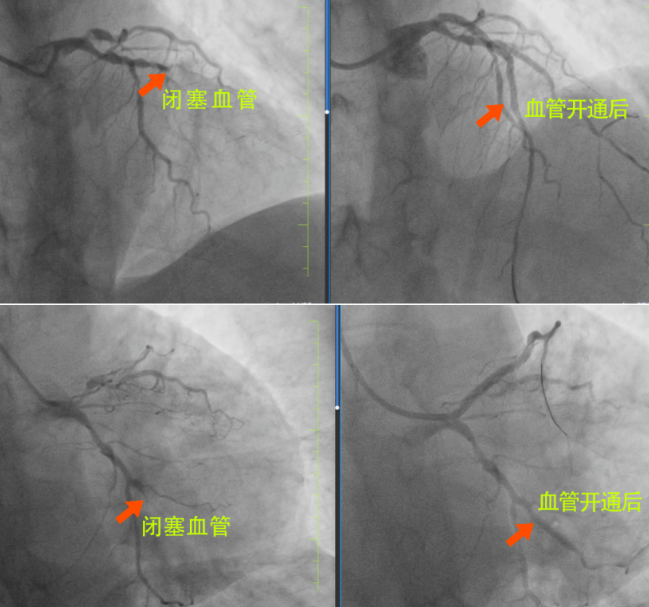

很快,長(zhǎng)春國(guó)文醫(yī)院心內(nèi)科為患者安排了手術(shù),為患者進(jìn)行手術(shù)的是長(zhǎng)春國(guó)文醫(yī)院副院長(zhǎng)、心血管中心主任隋立有。隋院長(zhǎng)在心血管領(lǐng)域造詣深厚,擁有豐富的臨床經(jīng)驗(yàn)。隋院長(zhǎng)始終專(zhuān)注于心血管疾病的研究與治療,對(duì)各類(lèi)復(fù)雜心血管病例有著獨(dú)到的見(jiàn)解和精準(zhǔn)的判斷。隋院長(zhǎng)在了解患者的病情后,迅速制定了治療方案?;颊?根血管完全閉塞,情況十分危急。但隋院長(zhǎng)憑借著精湛的醫(yī)術(shù)和豐富的經(jīng)驗(yàn),巧妙地開(kāi)通了2根血管,整個(gè)手術(shù)過(guò)程僅僅用了不到半小時(shí),就成功完成了3枚支架的植入。這一高效且精準(zhǔn)的手術(shù),讓患者和家屬驚嘆不已,也讓他們真切地感受到了國(guó)文醫(yī)院心內(nèi)科雄厚的師資力量和成熟的技術(shù)實(shí)力。